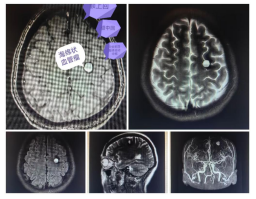

近日,阿坝州人民医院神经外科团队突破技术瓶颈,成功完成川甘青三省结合部区域首例多学科协作下中央区海绵状血管瘤切除术。该手术创新采用“术前放射精准定位+术中彩超实时导航+经脑沟入路显微技术”的综合方案,为一名病变位于大脑运动功能核心区的46岁女性患者解除病痛,标志着高原地区复杂脑功能区病变精准诊疗能力取得重大突破。

医院紧急启动多学科协作机制:放射科丁世荣主任带领团队通过精准标记技术锁定病灶边界及毗邻神经血管;超声科张伟主治医师创新采用浅表探头实现术中实时动态导航;神经外科团队严格遵循显微操作规范,经额上回及额中回脑沟入路完整切除病灶。术前精准制图与术中彩超导航的高效配合,成功弥补了高端设备缺口。

手术历时三小时顺利完成,出血量不足100毫升。患者术后即刻清醒,未出现肢体功能障碍、语言障碍或癫痫发作等并发症,右侧肢体肌力及感觉均保持术前水平,恢复进程良好。此例手术的成功实践,彰显了多学科协作模式下精准医疗理念的落地成效,填补了川甘青三省结合部区域高风险脑功能区病变精准手术的技术空白,为高原地区神经外科诊疗水平提升树立新标杆。阿坝州人民医院将持续深化精准医疗探索,强化区域医疗协作,为各族群众提供更优质高效的医疗服务。